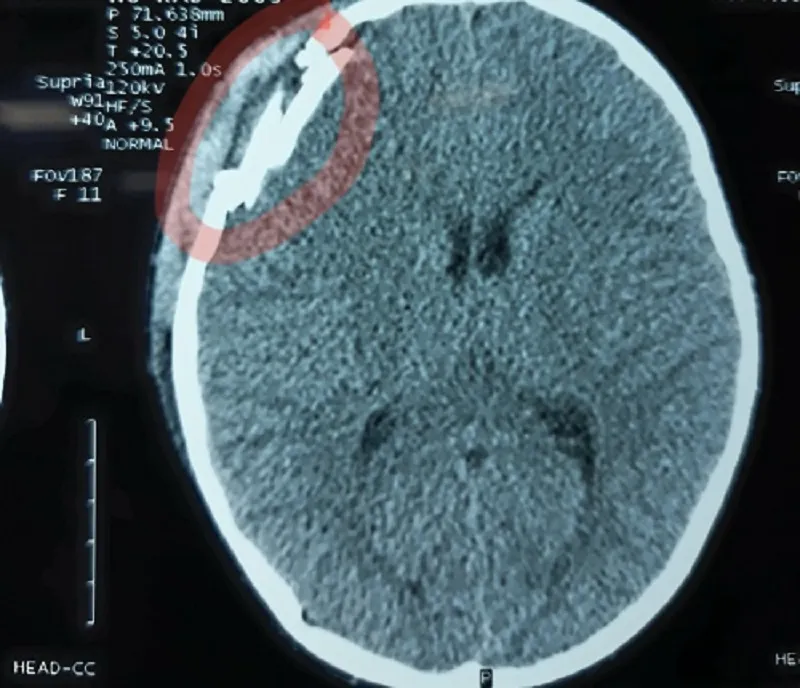

Ngay sau đó em Đ. được đưa đi cấp cứu tại Bệnh viện Hữu nghị Cu Ba - Đồng Hới trong tình trạng đau đầu, chóng mặt, chảy máu mũi. Qua chụp phim CT Scanner cho thấy nạn nhân bị chấn thương sọ não, vỡ xương sọ vùng trán và tụ máu ngoài màng cứng.

Ảnh chụp phim CT Scanner.